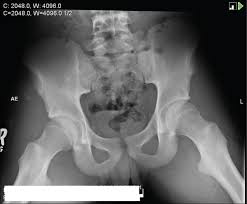

Hip pain in children is always a potentially serious and needs urgent assessment. Call 999 and ask for an ambulance. They are serious injuries that most often occur in people aged 65 and older. I am 15 and did it to my hip/ upper pelvic bone. They usually happen when a bone is moving one way, and a tendon or ligament is suddenly pulled the opposite way.

Timely, accurate diagnosis is imperative so proper treatment can be initiated. Ebraheim's educational animated video describes the condition of avulsion fractures around the hip in adolescence. Call 999 and ask for an ambulance. I was doing high jump and twisted my body and in the process my muscle ripped my growth bone off. Hip fractures are classified according to their anatomical location as intracapsular, which involves the femoral head and neck, and extracapsular, which includes intertrochanteric, trochanteric, an. With an avulsion fracture, an injury to the bone occurs near where the bone attaches to a tendon or ligament. Symptoms of ankle avulsion fracture are similar to ankle sprain. Call your health care provider if your pain doesn't go away, or if you notice swelling. Preparing for an avulsion fracture in the ankle? Avulsion fractures of the hip and. Avulsion fracture of the iliac crest is an uncommon pathology. This happens when a muscle or tendon connected to the hip bone suddenly tightens so hard that it pulls off part of the bone. I am 15 and did it to my hip/ upper pelvic bone.

Hip Pain In Athletes American Family Physician from www.aafp.org Call your health care provider if your pain doesn't go away, or if you notice swelling. Symptoms of ankle avulsion fracture are similar to ankle sprain. Teenagers are more likely to have this injury than younger children. Avulsion fractures can be classified as acute, subacute or chronic. A broken hip usually requires surgery for treatment. The causes of hip fracture are very different in young and elderly patients. In some cases, surgery is required. A hip fracture is a common injury, especially in people with osteoporosis.

With an avulsion fracture, an injury to the bone occurs near where the bone attaches to a tendon or ligament. Anyone can suffer an avulsion fracture of the ankle, but athletes and children are more prone to them than the rest of us. This happens when a muscle or tendon connected to the hip bone suddenly tightens so hard that it pulls off part of the bone. Ebraheim's educational animated video describes the condition of avulsion fractures around the hip in adolescence. An avulsion fracture occurs when a small chunk of bone attached to a tendon or the hip, elbow and ankle are the most common locations for avulsion fractures in the young athlete. If you think you've fractured your hip, you'll need to go to hospital as soon as possible. In acute avulsion fractures, there is usually a clear preceding traumatic incident. When to seek medical help. The causes of hip fracture are very different in young and elderly patients. With age, the bones can become weak and brittle. Other causes include cancer and injury. They usually happen when a bone is moving one way, and a tendon or ligament is suddenly pulled the opposite way. Hip apophyseal injuries in young athletes are a fairly rare problem, and often go unrecognized by health professionals.

Acute Avulsion Of The Iliac Crest Apophysis In An Adolescent Indoor Soccer from www.jbsr.be I am 15 and did it to my hip/ upper pelvic bone. An avulsion fracture is a fracture in which part of the bone breaks off from the rest of the bone. When the fracture happens, the tendon or these fractures most often affect bones in the elbow, hip, and ankle. What causes a hip fracture? There are numerous sites at which these occur. Hip pain in children is always a potentially serious and needs urgent assessment. Teenagers are more likely to have this injury than younger children. Hip fractures can limit mobility and independence.

Pain in the hip area may be referred from the knee joint or from structures in the inguinal canal, testis (including torsion) and lower abdomen, or from the lower back. Teenagers are more likely to have this injury than younger children. The causes of hip fracture are very different in young and elderly patients. Other causes include cancer and injury. Hip fracture occurs in approximately 341,000 persons in the united states each year. Read about causes, treatment options, available mobility devices, tips for recovery, and more. This happens when a muscle or tendon connected to the hip bone suddenly tightens so hard that it pulls off part of the bone. In acute avulsion fractures, there is usually a clear preceding traumatic incident. A hip fracture is a break in the bones of your hip. A hip fracture is a common injury, especially in people with osteoporosis. I was doing high jump and twisted my body and in the process my muscle ripped my growth bone off. A broken hip in older people is often partly the result of weakening bones from osteoporosis. This most commonly occurs at the ischial tuberosity where the hamstrings attach, or the iliac pain at the bony part on the front of the hip may be an anterior superior iliac spine avulsion fracture.